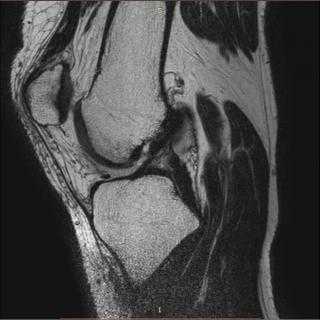

Повреждения сухожилий четырехглавой мышцы бедра

Нога человека сгибается в колене благодаря наличию мышцы-разгибателя, расположенной на передней части бедра. Она называется четырехглавой мышцей - состоит из четырех пучков мышечных волокон, каждый из которых имеет свое название. Все составляющие квадрицепс-мышцы имеют общее сухожилие, прикрепленное к надколеннику. Оно достаточно эластично и обладает высокой прочностью. А вот места перехода мышцы в сухожилие и крепления сухожилия к кости являются точками уязвимости квадрицепса при различных травматических воздействиях.

Чаще всего сухожилия четырехглавой мышцы бедра подвержены растяжению, частичному или полному разрыву, а также тендиниту - воспалительному процессу ткани сухожилия.

Симптомы повреждений сухожилий четырехглавой мышцы бедра

Момент повреждения сухожилий четырехглавой мышцы бедра сложно не заметить. При травмировании происходит щелчок или хлопок, и человек теряет способность к передвижению, хоть в некоторых случаях и не полностью. При полном разрыве сухожилия выпрямить колено невозможно. Нарастает отек, сохраняется острая боль, в месте разрыва можно нащупать образовавшийся дефект. Ткани чуть выше коленной чашечки выглядят запавшими, возможны судорожные спазмы мышц бедра. Наколенник опускается ниже положенного, но из-за отека это может быть сложно рассмотреть.

Если разрыв сухожилия происходит постепенно, вследствие дегенеративных процессов в тканях, то установить диагноз бывает сложно. Жалобы и данные осмотра говорят о растяжении связок, что затрудняет постановку правильного диагноза и начало лечения.

Диагностика повреждений сухожилий четырехглавой мышцы бедра в клинике

О наличии повреждений сухожилий четырехглавой мышцы бедра говорят трудности с ходьбой, своеобразная походка с низкой вовлеченностью в процесс колена, "провалы" колен. Просьбу поднять прямую ногу пациент выполнить не может. Чем серьезнее травма, тем менее подвижно колено. Врач осматривает обычно не только поврежденное колено, но и здоровое, чтобы исключить его поражение.

Методы визуализации при диагностике повреждений сухожилий четырехглавой мышцы бедра являются вспомогательными и не имеют особой диагностической ценности. Их используют для уточнения характера дефекта и степени повреждений.